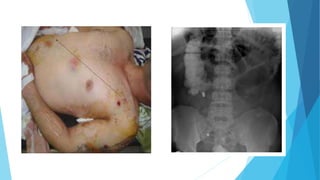

CASE 1

 A 47 years old man, involved in RTA 7 hours ago, arrived

to the A&E Department.

 1-IS THERE ANY SIGN OF ABDOMINAL INJURY?

 2-NAME OF THE SIGN

CASE 1 Abdominal examination: distended abdomen,

absence of bowel sounds, no guarding or

tenderness, no abdominal pain. Normal pulse

and blood pressure.

 4.What is the next step in the treatment?

 LAPAROTOMY OR REQUEST INVESTIGATIONS???

 5-Which investigations will you need in order

to determine the cause of the abdominal

distension.

 FAST

Positive or negative????

Treatment. Explain

 Positive or negative???

 Next Step in the management????

 CT scan

 Positive or negative?????

 Treatment. Explain.

Chest x ray

Positive or negative???

Explain

Treatment